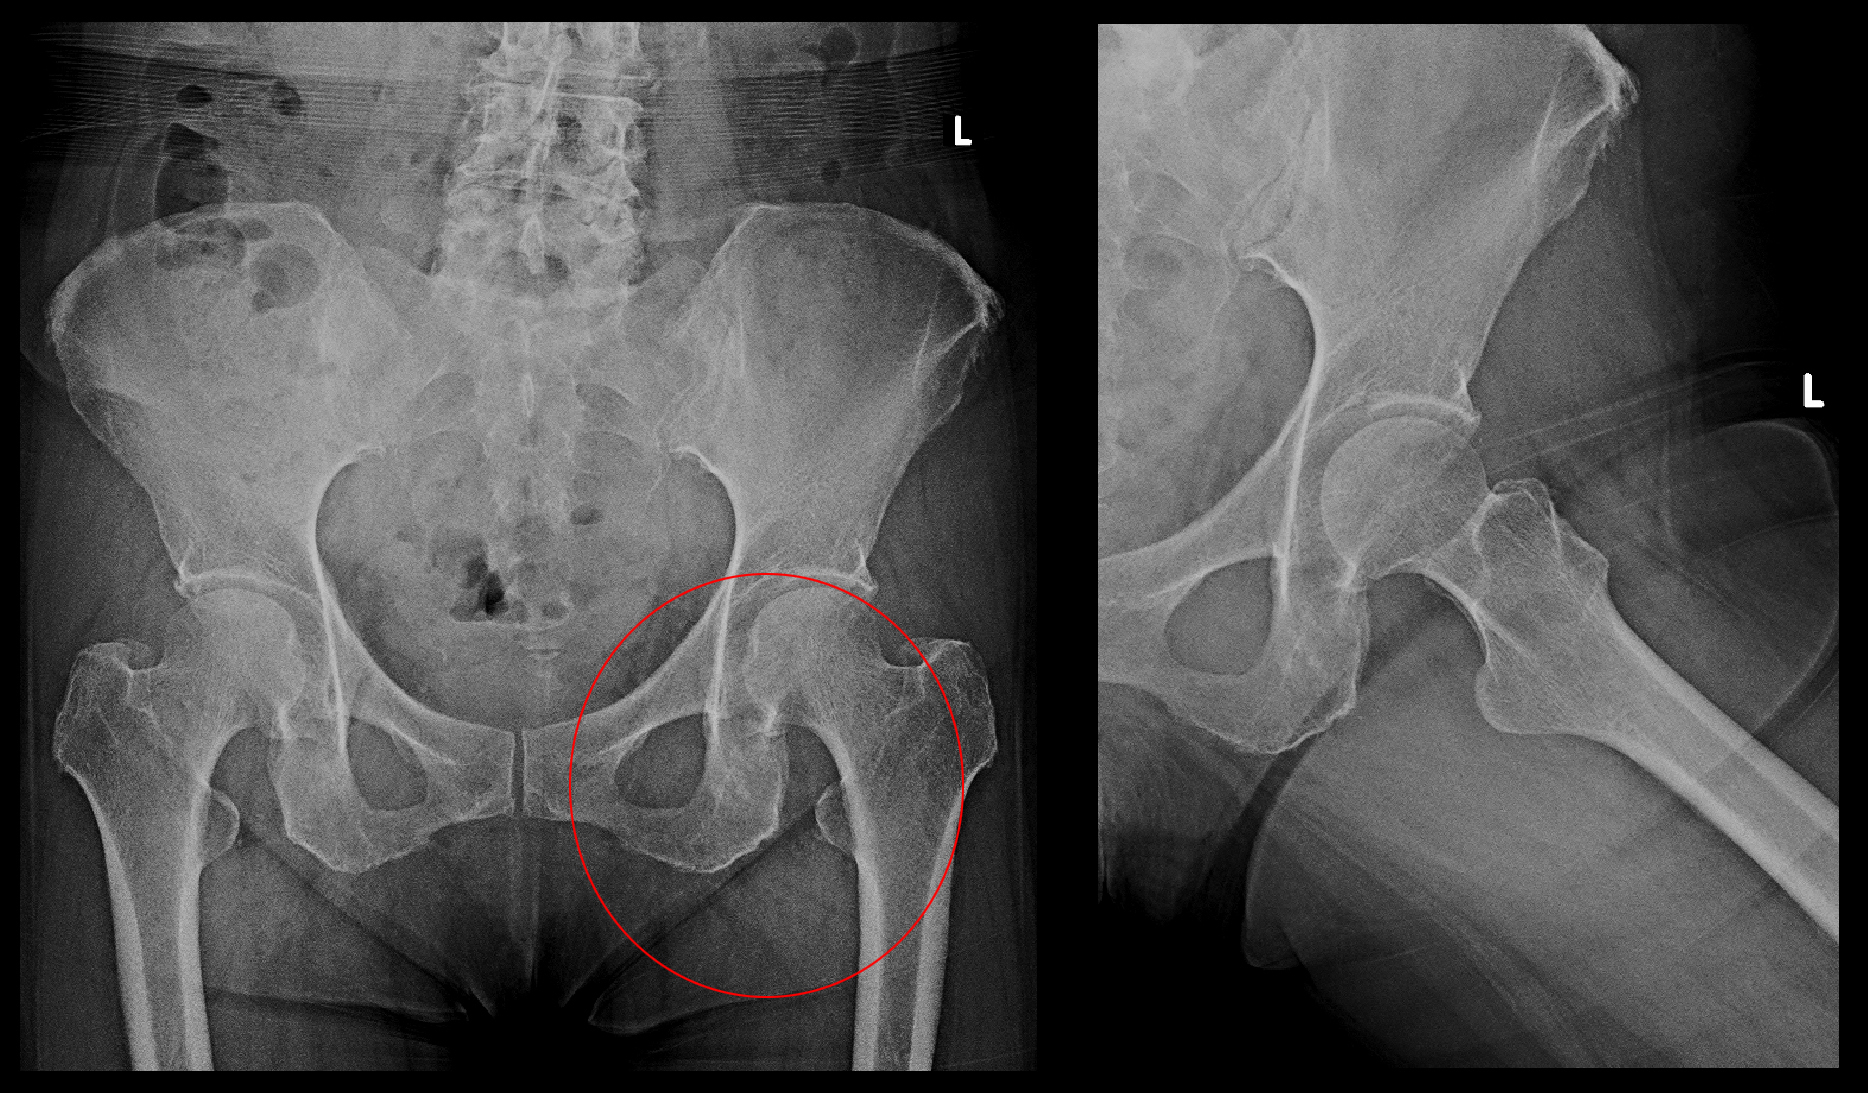

65才女 Xp.jpg臀部痛・大腿部痛の患者さんでは股関節の異常の有無をチェックしますが、左股関節の異常を疑わせる理学所見がみられたため、股関節と腰椎のMRI検査を行いました。